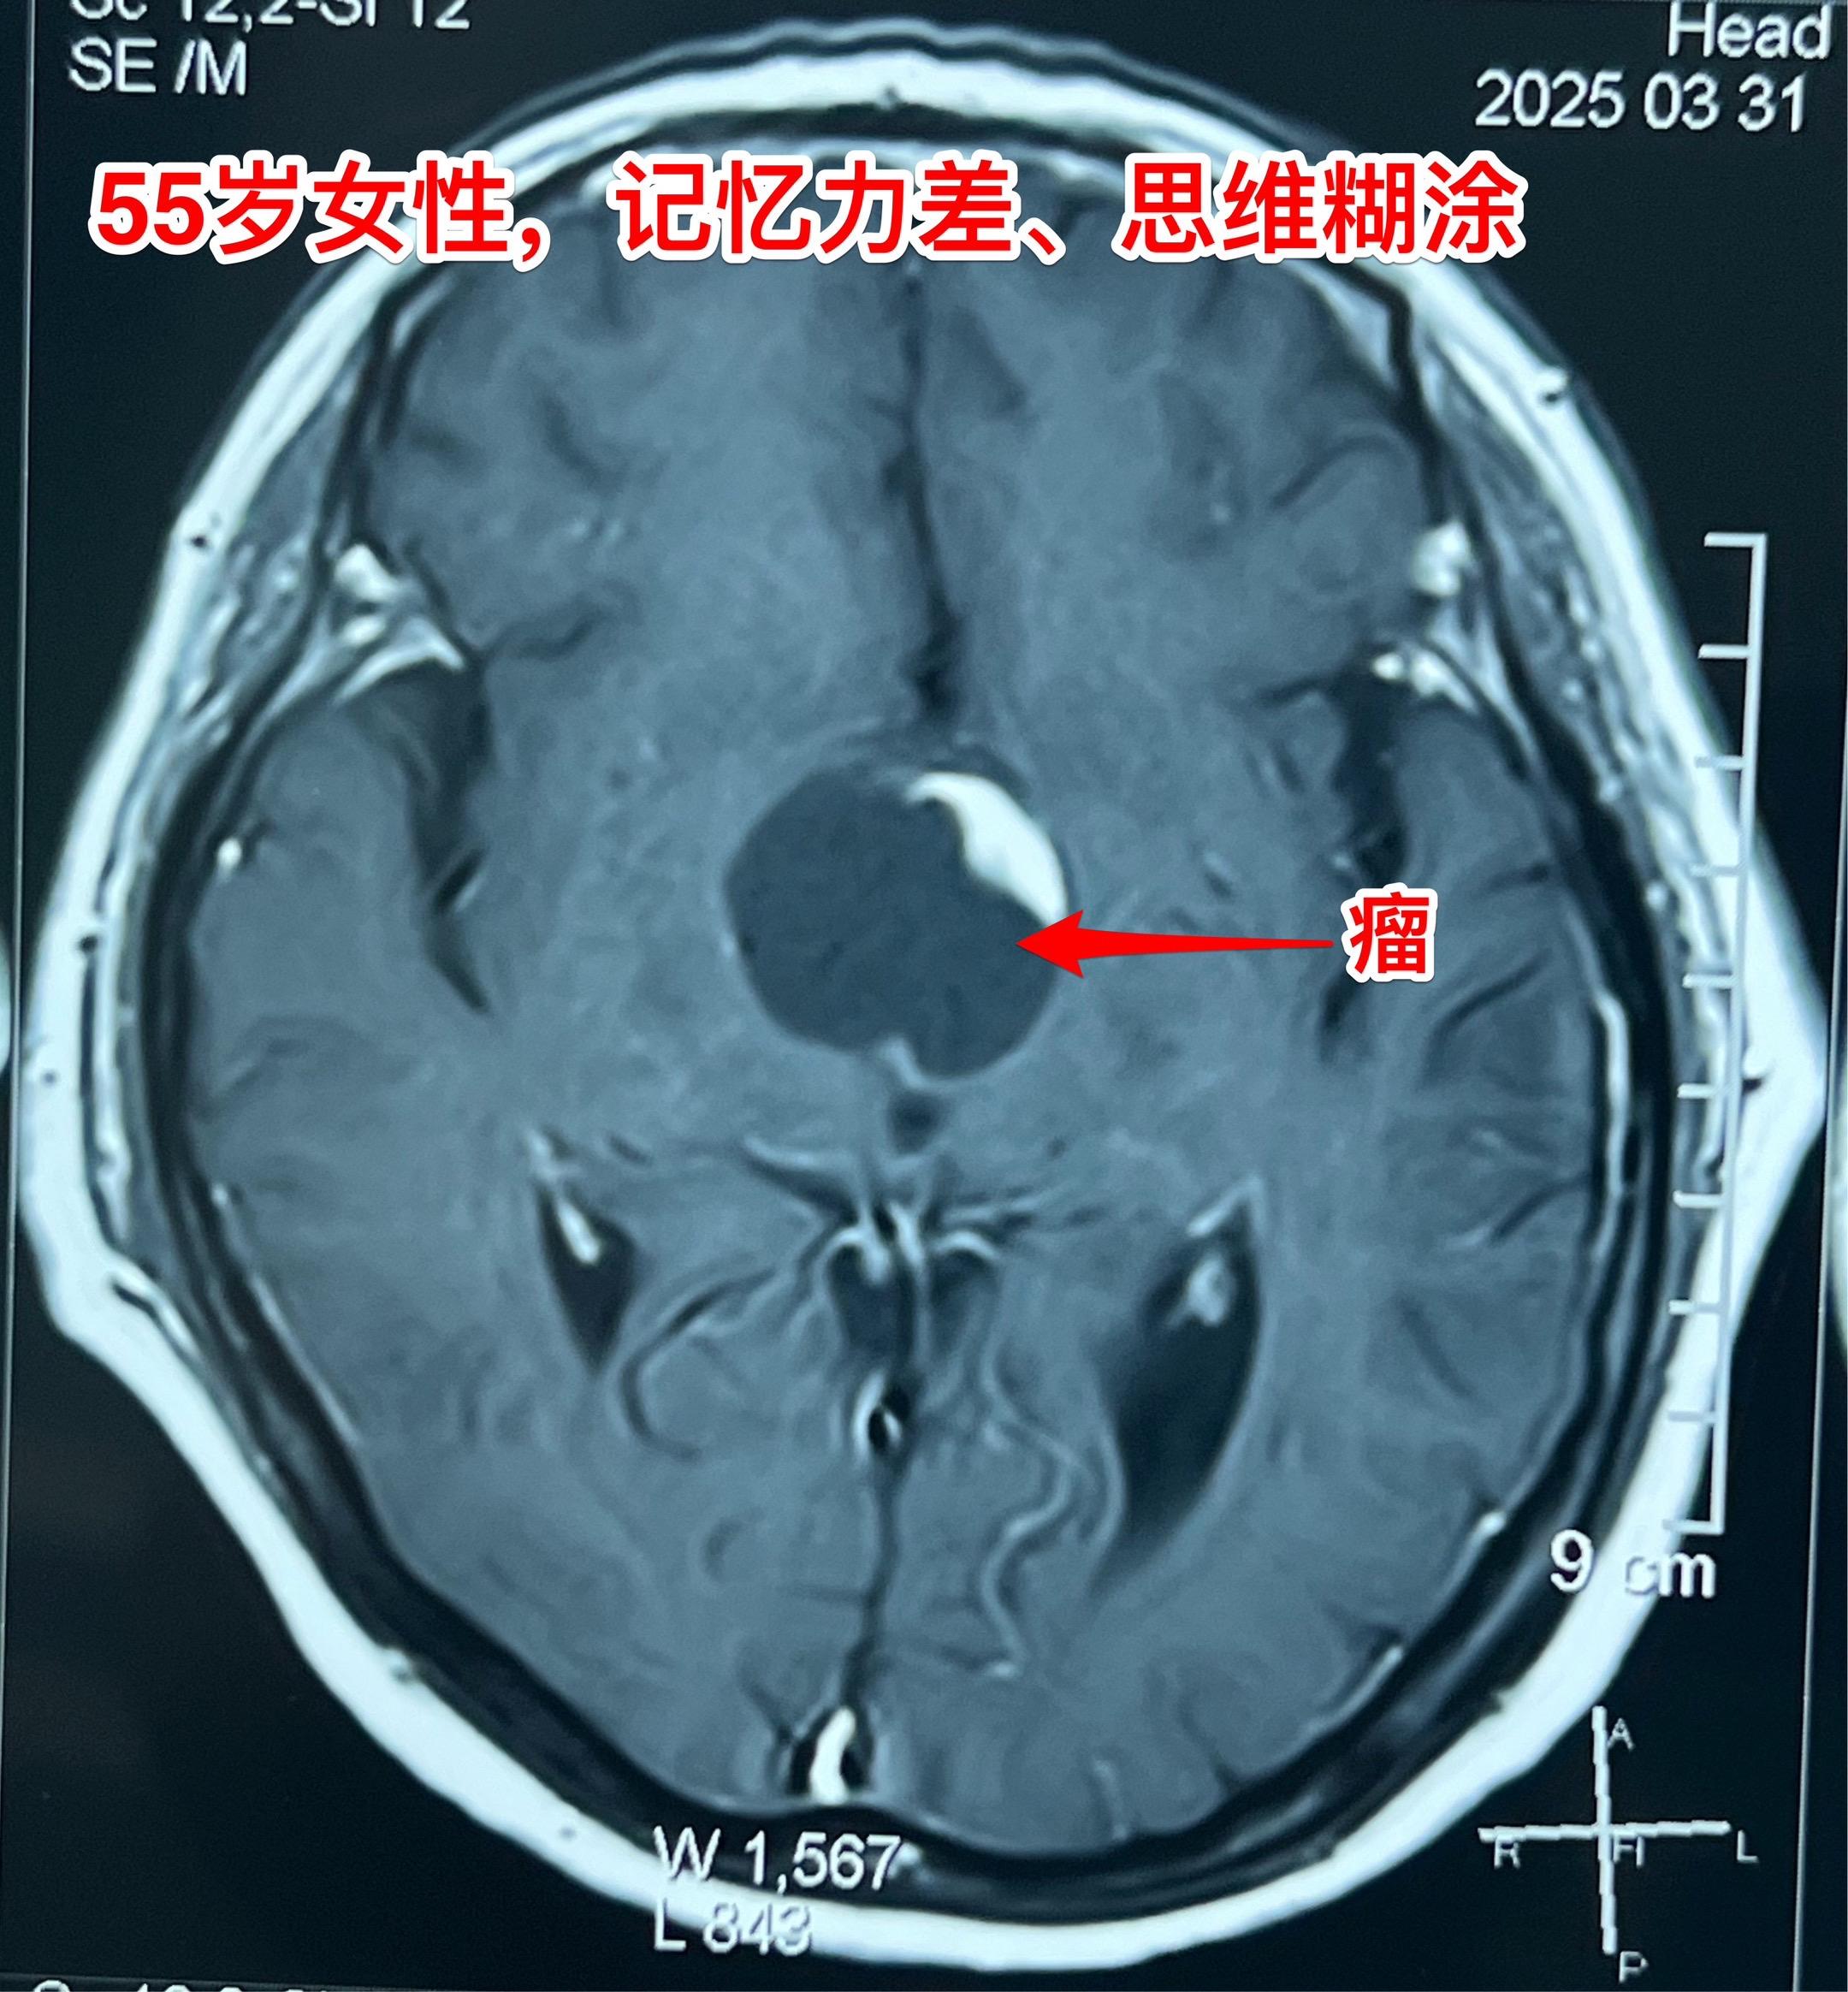

第一眼就诊断为颅咽管瘤,病理报告却不是。55岁女性因记忆力下降,有时思维糊涂就医,行脑部磁共振和CT检查发现鞍上区域囊性肿瘤,伴有钙化。 鞍上的囊性肿瘤伴有钙化,病人年龄55岁,第一印象就是颅咽管瘤。这是常规思维。 手术中发现肿瘤边界不清楚,肿瘤的钙化也不是颅咽管瘤那样的白色钙化,送了两次快速冰冻病理检查,报告提示是胶质瘤。 临床上看病首先考虑的是常见病,读书的时候老师就是这样教的。 事实上,临床上常见病能见到,罕见病也能见到。通常情况下下丘脑胶质瘤是